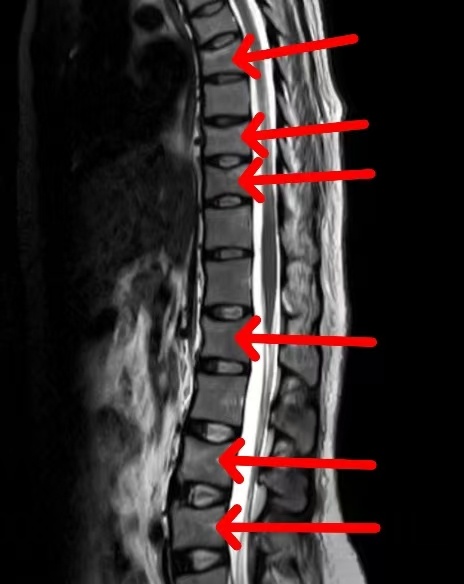

患骨质疏松的新手妈妈胸椎、腰椎发生多节段压缩性骨折

让夏冬冬印象格外深刻的还有之前诊治过的一位新手妈妈,当时她和侯女士一样,也在产后突发腰背部疼痛,磁共振检查结果显示其胸椎、腰椎发生多节段压缩性骨折,进一步的骨密度检查结果则显示其骨密度远远低于同龄正常人,甚至比80岁老太婆的骨密度还差。

“一般来说,孕期及哺乳期女性因为突发腰背部疼痛到医院来看,如果磁共振检查出有脊柱压缩性骨折,基本就可以确诊为骨质疏松了。因为骨质疏松最常见、也最严重的表现之一就是脆性骨折,也就是未受到暴力就发生了骨折。”夏冬冬说,相比于一般的骨质疏松患者,妊娠及哺乳期骨质疏松症患者往往有骨密度更低、骨折更多的特点,而且骨折多是脊柱骨折,如果处理不善,很容易引发脊柱后凸畸形,导致驼背、身体变矮。